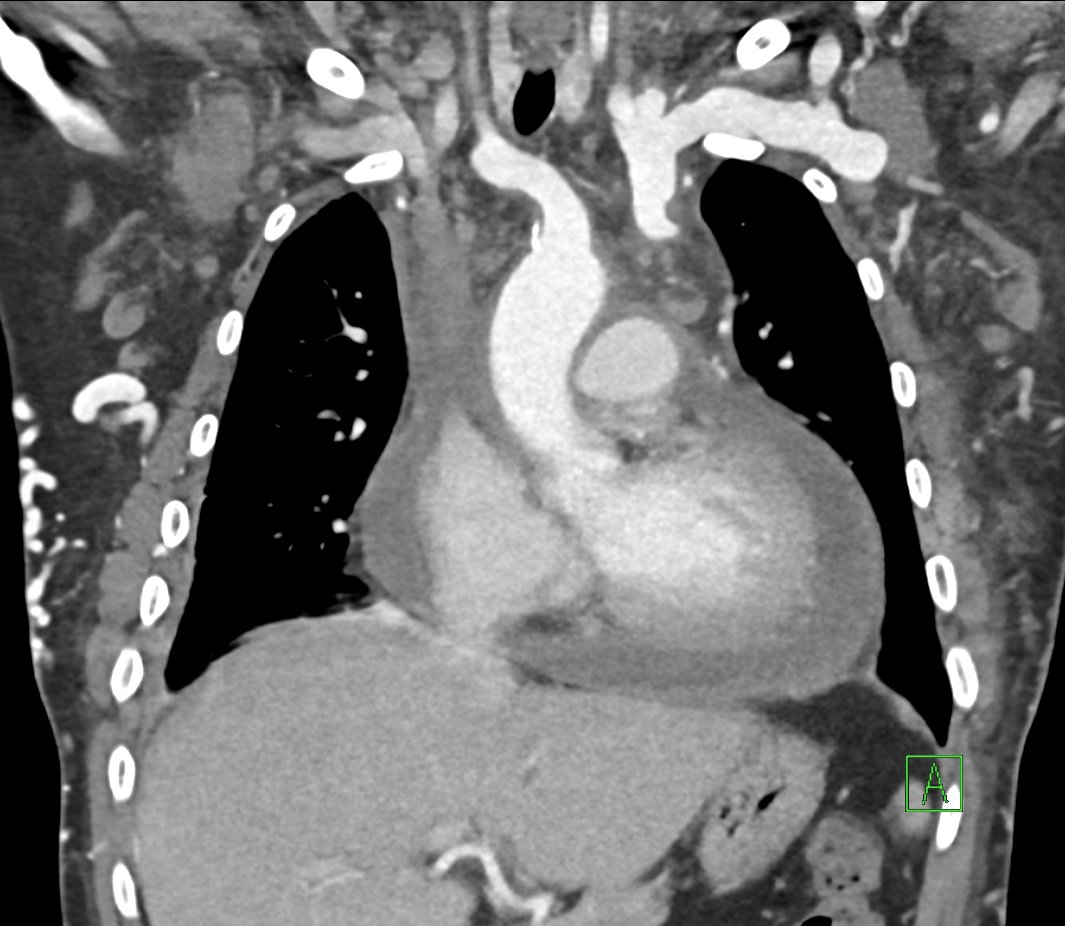

#SVC recanalization & left#innominate#venoplasty for a patient with refractory#hemopericardium and#SVC syndrome#Makkah#IRad#InterventionalRadiology#Radiology#Makkahpic.twitter.com/uaGWjQVTj0